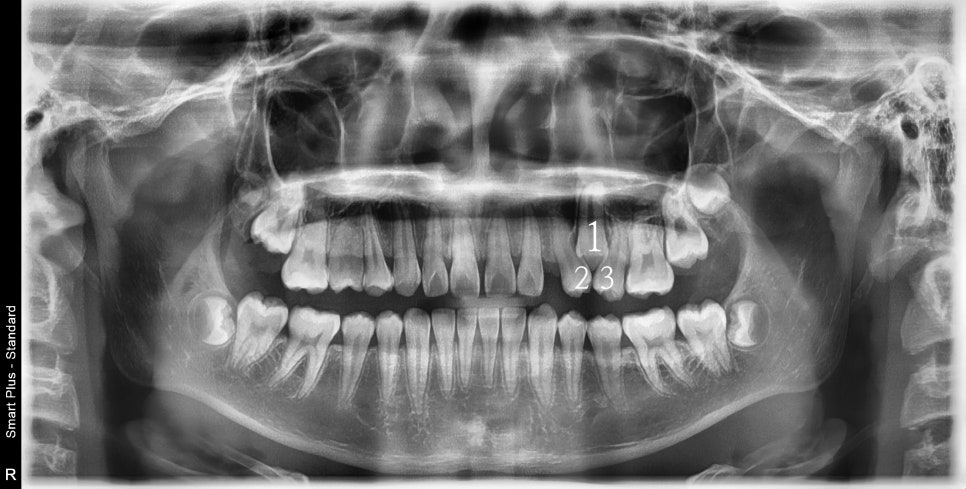

사진상 2 1 3 이라고 표시된 치아의 원래 순서는 1 2 3 입니다.

가끔 이렇게 치아가 만들어지면서 치아의 씨앗 위치가 바뀌면서 뒤죽박죽이 되는 경우가 있습니다.

어느정도라면 원래의 순서로 배열하기도 하지만, 이 친구는 2 1 3 순서로 배열하기로 했어요.

두번의 계획으로 나눴습니다. 처음 6개월은 1이 내려오기 위한 공간을 만들기.

두번째 세트 제작에서 1을 배열하기로 나눴습니다.